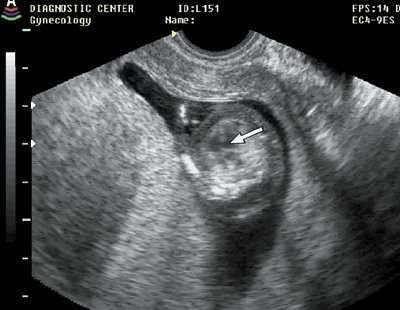

Рис. 4. Гастрошизис (стрелка), беременность 13 недель 1 день.

Рис. 5. Мегацистис (стрелка), беременность 11 недель 3 дня.

Рис. 6. Иниоэнцефалия, беременность 11 недель 6 дней.

Рис. 7. Диафрагмальная грыжа (стрелка), беременность 11 недель 4 дня.

Рис. 8. Дефект межжелудочковой перегородки (стрелка), беременность 12 недель.